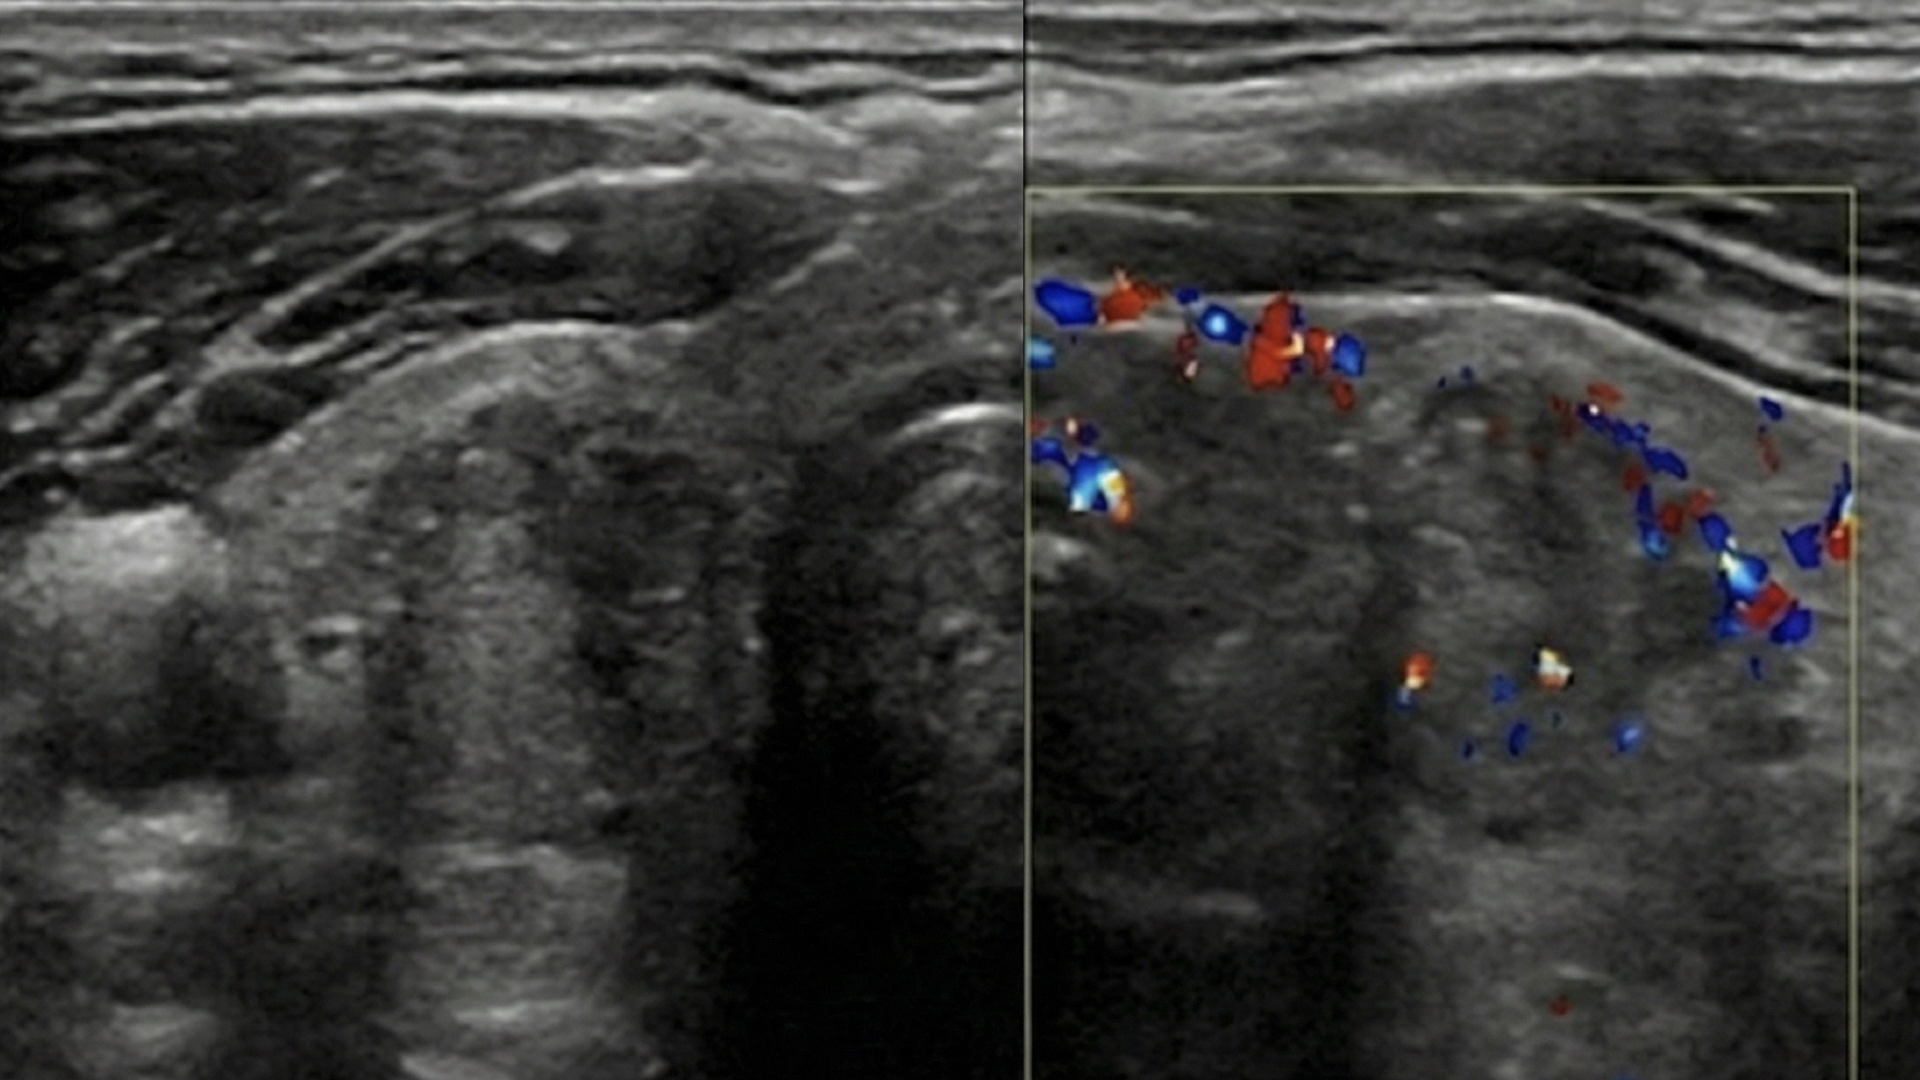

- ◈ Vascularidad Periférica o Caótica: Flujo sanguíneo desorganizado. Sensibilidad: 86%, Especificidad: 82%. Superior a la vascularidad hiliar central (benigna).

- ◈ Pérdida del Hilio Graso: Ausencia o borramiento del hilio ecogénico central. Nota: Un hilio preservado tiene un VPN del 100% (Sens: 100%, Espec: 29%).

- ◈ Morfología Redondeada: Índice eje largo/eje corto < 2.0. Los ganglios benignos son ovoides; los malignos tienden a la circularidad.